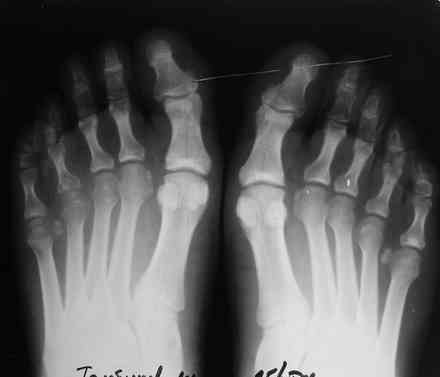

Уважаемые коллеги. Помогите определиться с диагнозом. Мужчина 28 лет обратился с жалобами на боль в правой стопе, усиливающиеся с утра "пока не расходишься".

Боль беспокоит на протяжении 4 мес, Имеется незначительная припухлость. болезненность при пальпации головок 4,5 плюсневых костей справа, кожа не измененена. Лабораторные данные в пределах нормы, хронических инфекций нет. рентгенологически имеется остеопороз головок 4,5 плюсневых костей справа.